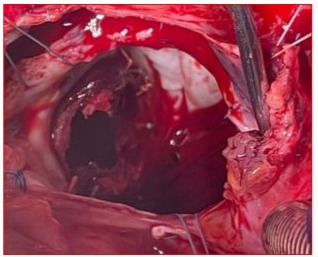

Sternotomy done with electric saw; thoracic cavity dissected. Vancomycin given, propofol and fentanyl-maintained anesthesia. CPB established with cannulas in aorta and veins. Heparin injected; ACT monitored. Normothermic CPB initiated, ventilation reduced during bypass, and cessation of ventilation during full-flow CPB (Figure 6). Endotracheal sevoflurane stopped, Diprivan AIVOC continued with fentanyl reinjection via CPB circuit. Antegrade cardioplegia started using trocar in aortic root. Mechanical mitral valve had total thrombosis with fresh and old thrombi filling valve ring. Leaflets blocked (Figure 7) After thorough washing and cleaning of the valve with saline, multiple ventricular thrombi were removed, successfully restoring full function to the mechanical valve. (Figure 8,9).

Figure 7 : Surgical image after right arteriotomy and expanded transseptal approach at the roof of the left atrium showing the appearance of the St. Jude mechanical valve completely thrombosed, encompassing the ring, both leaflets, and the core.

Figure 8: Perioperative image showing the St. Jude mechanical valve partially cleaned in its initial anatomical anti-position during the extraction of remaining thrombi using forceps on the atrial side (a) (black arrow), the ventricular side (b) on the internal and external leaflets, and at the level of the coated ring (c, d) (blue arrows).

Figure 9: Surgical image showing a clean appearance of the St. Jude Medical mitral valve after being completely cleared of thrombi following saline washing, returned to its anatomical position, and opened freely around its pivot with both the anterior and posterior leaflets.